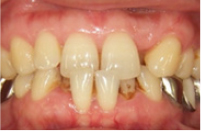

治療例2

| 初診時年齢 | 53歳 |

|---|---|

| 主訴 | 歯のガタガタが気になる |

| 診断名 | 叢生を伴う下顎前突 |

| 治療に用いた装置 | リンガルブラケット矯正装置 |

| 抜歯部位 | 非抜歯 |

| 治療期間 | 1年4ヶ月 |

| 費用の目安 | 1,250,000円~ |

治療前

治療後